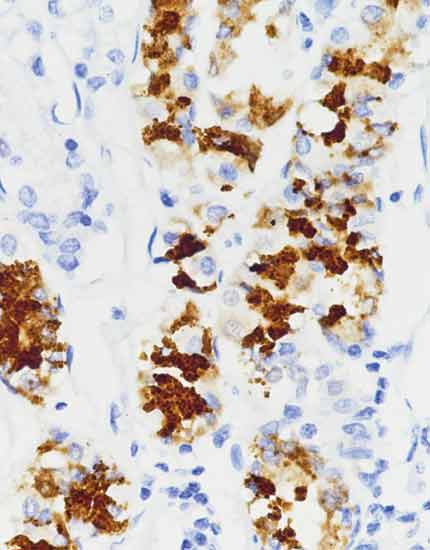

产品名称:PRAME

产品编号:RMA-1047

阳性部位:细胞核

图片描述:

恶性黑色素瘤,PRAME染色,细胞核阳性